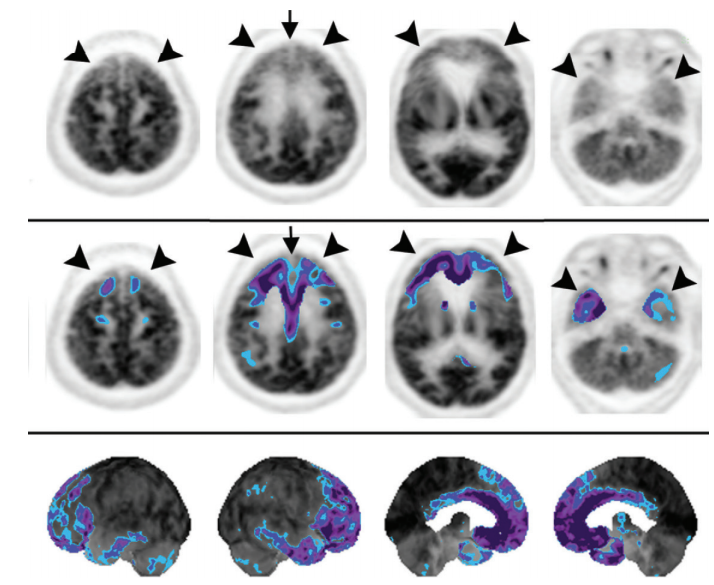

If the frontal lobe or internal capsule is involved, hypometabolism in the contralateral cerebellum may be seen due to crossed cerebrocerebellar diaschisis

misregistration due to patient motion

atrophy –> sulcal widening –> artifact of hypometabolism (pitfall for misdiagnosis of neurodegenerative disorder)